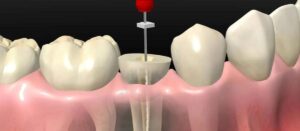

سحب عصب الأسنان أو حشو العصب هو إجراء علاجي يتم تنفيذه للحفاظ على السن في حالات التسوس الشديد والعدوى، ويشمل الإجراء إزالة لب السن وكل الأعصاب والأوعية الدموية المتواجدة به، تنظيف تجويف اللب، ومن ثم حشو السن. يُعرف هذا الإجراء طبيًا بـ “معالجة قناة الجذر” أو “العلاج اللبي”.

خطوات سحب عصب الأسنان:

يتم إجراء سحب العصب على مراحل، ويشمل العديد من الخطوات:

- إزالة لب السن: يتم إزالة لب السن بعناية للتخلص من الأنسجة والأعصاب، ويمكن أن يشمل ذلك تصريف الخراج إذا كان موجودًا.

- تنظيف اللب وملء قناة الجذر: يتم تنظيف تجويف اللب وتطهيره للتأكد من خلوه من البكتيريا، ثم يتم ملء قنوات الجذر استعدادًا للمرحلة التالية.

- غلق قناة الجذر وحشو السن: يتم إغلاق قنوات الجذر بمادة خاصة لمنع التسرب وحشوها بشكل كامل، ثم يتم وضع حشوة لإغلاق السن.

- وضع تلبيس الأسنان أو التاج: بعد سحب العصب، يتم وضع تلبيسة أو تاج على السن لتقويتها وحمايتها.

ويراعى أن يتم وضع تلبيس الأسنان بعد تقليم السن أولاً، ثم تُخذ القياسات وتُصنع التلبيسة لتناسب السن بدقة، وتوفير حماية إضافية للسن المعالج.